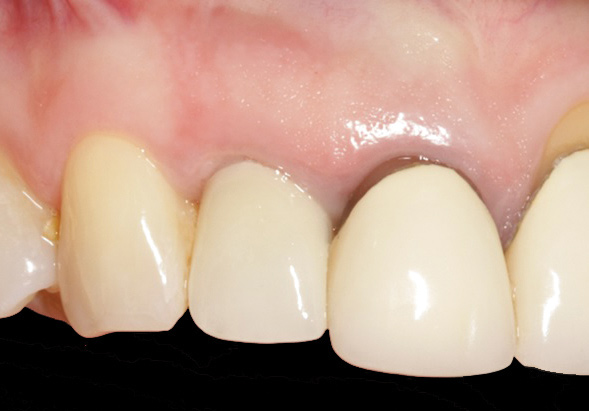

Fig 3. Initial buccal view of tooth No. 7.

Figure 3

To predict peri-implant esthetic outcomes, Kois described five essential diagnostic keys that need to be assessed before removing a periodontally hopeless tooth (Figure 3 and Figure 4): (1) relative tooth position; (2) form of the periodontium; (3) periodontal biotype; (4) tooth shape; and (5) position of the osseous crest. Failing teeth that have a thick, flat gingival biotype, are square shaped, and have < 3 mm vertical distance from the position of the facial and interproximal crest have the lowest risk of developing recessions after implant placement.23 Therefore, implant surgery may be performed by either an open flap or flapless approach. However, teeth with a thin soft-tissue biotype, a highly scalloped gingival architecture, and a triangular shape that are positioned facially have less-predictable peri-implant esthetic outcomes. When a tooth presents with these unfavorable anatomical features, grafting procedures should be considered both before and after tooth extraction to prevent vertical loss and facial collapse of the gingival architecture.21 Flapless tooth extraction should be attempted in the esthetic zone to maintain blood supply from the periosteum and endosteum and maximize healing potential (Figure 5).44 In addition, several surgical protocols have been proposed to avoid peri-implant mucosal recessions, including 3-dimensional implant positioning,45,46 the use of platform-switching implants,47,48 and soft-tissue augmentation.8,49,50